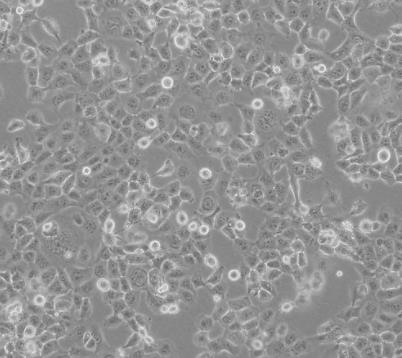

NCI-H460人大细胞肺癌细胞

NCI-H460人大细胞肺癌细胞是从一位大细胞肺癌患者的胸水中建立的。NCI-H460细胞表达的p53

mRNA易于检测,水平与正常肺细胞相当,未表现出NCI-H460细胞DNA总体结构异常。NCI-H460细胞角蛋白和波形蛋白纤维染色阳性;神经丝三联体蛋白阴性。